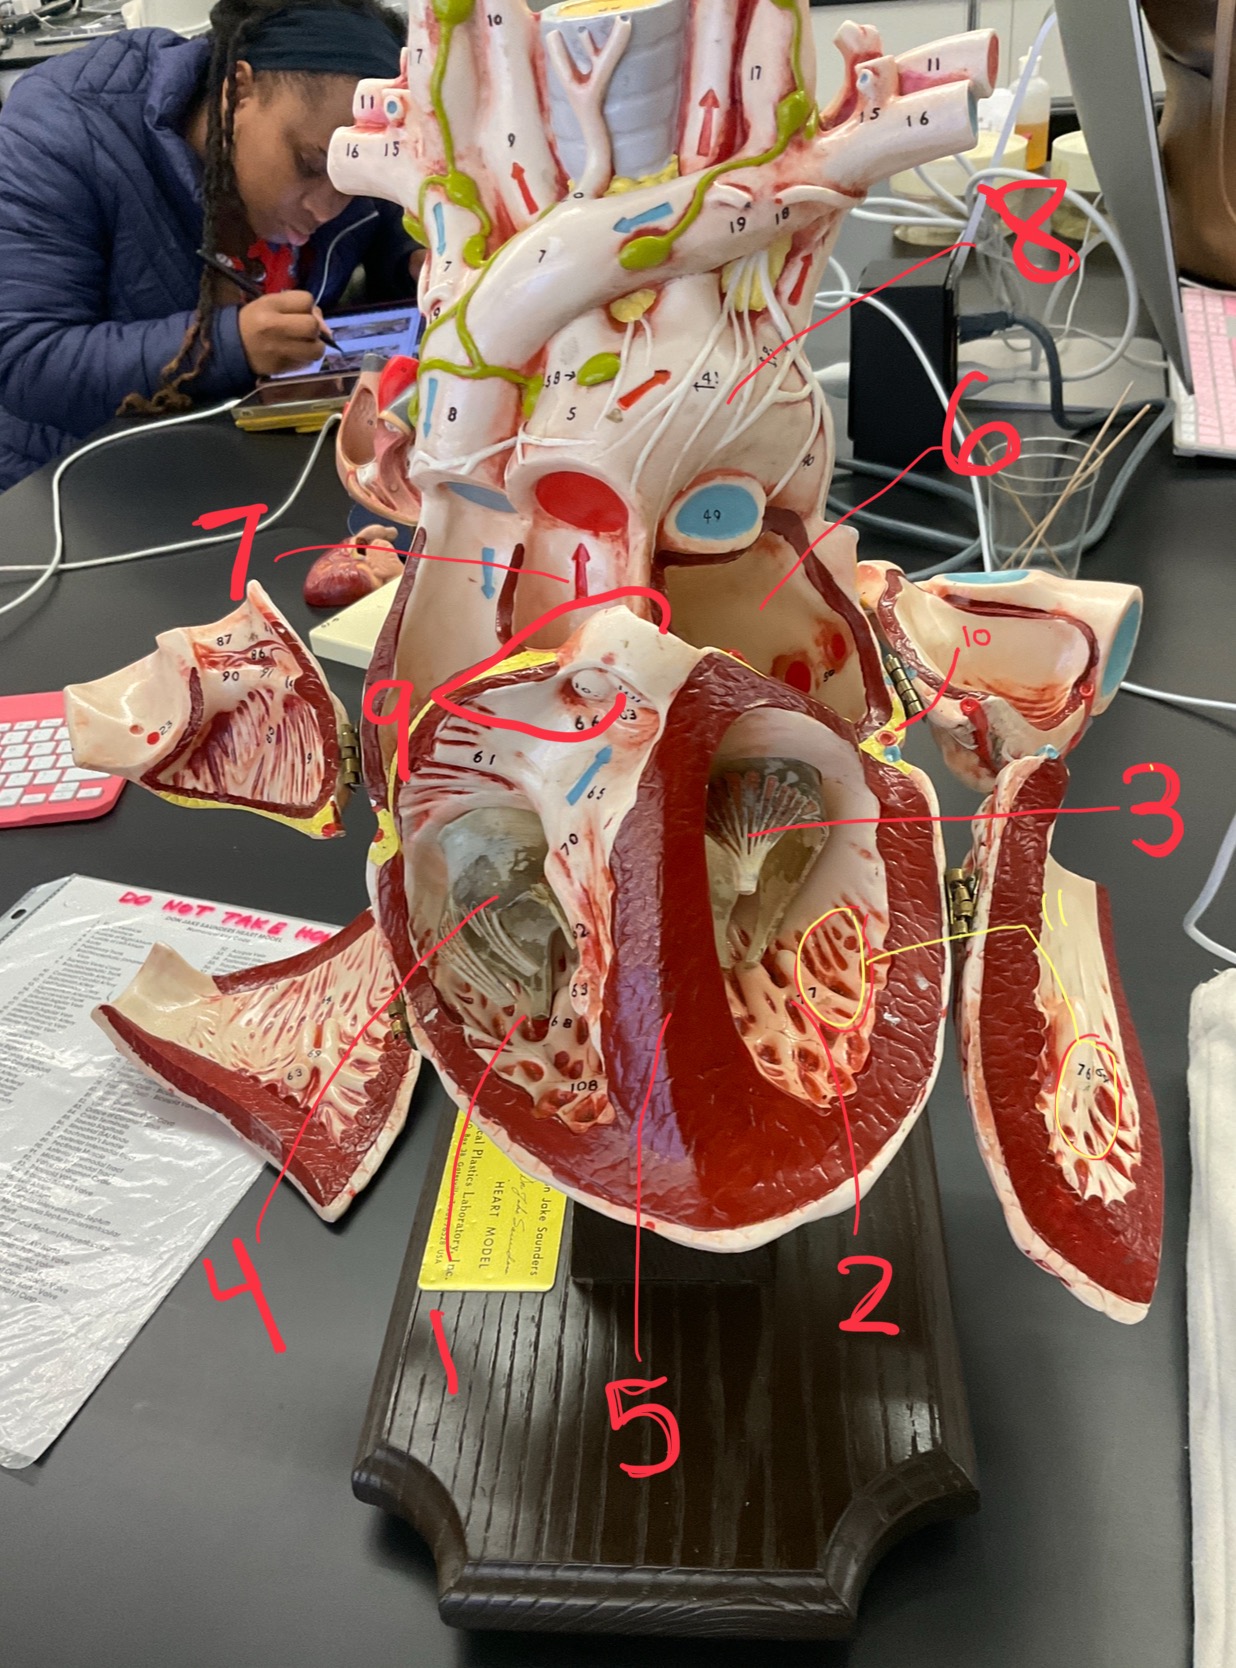

1

epicardium

2

3

endocardium

3

2

myocardium

4

1

coronary sinus

5

2

inferior vena cava

6

3

superior vena cava

7

1

right ventricle

8

2

left ventricle

9

3

bicuspid

10

4

tricuspid

11

5

interventricullar septum

12

6

left atrium

13

7

aorta

14

8

aortic trunk

15

9

pulmonary semi-lunar valve

16

10

atrevoventricullar sulus

17

11 (not smooth part)

trubeculae carneae

18

1

papillary muscle

19

2

chordae tendineae

20

4

pulmonary trunk

21

6

aortic trunk